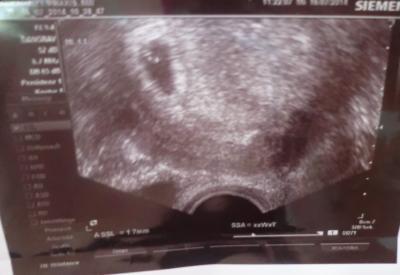

ich war jetzt die ganze zeit nicht da... Hab zur zeit echt privaten stress... Ich werde am Freitag die Kugelliste Aktualisieren!!! Aktuell bin ich froh mal eben ruhe zu haben.. Durch den ganzen Stress/streit (NICHT!! Mit mann) hatte ich magenschmerzen, die war schlecht und schwindelig. Deshalb war ich ausser der reihe heute beim arzt. Fruchthöle (1,4 cm) dottersack und Baby (1,7 mm) ist zu sehen.. herzchen hat noch nicht geschlagen.. Hab am 24.07 dann meinen Termin ;) Bis freitag dann Lg